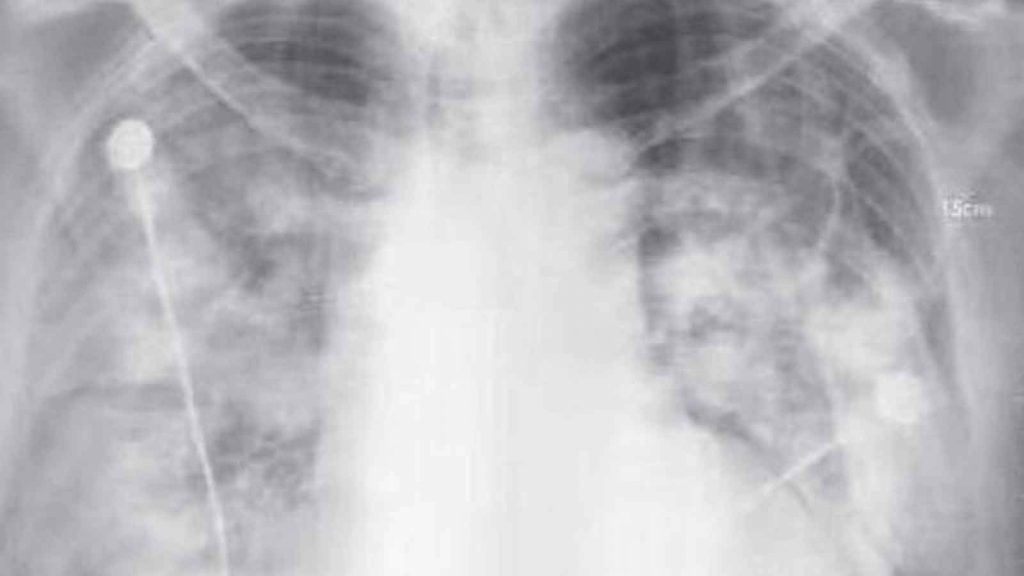

El especialista en infectología mexicano Juan Luis Mosqueda compartió imágenes de ese reporte, en las que se muestran radiografías de tórax de dos de los primeros pacientes contagiados y atendidos en la nación asiática.

En entrevista, el médico explicó que se detectó que la neumonía causada por el coronavirus 2019-nCoV afecta los dos pulmones de las personas, lo que indica que puede desarrollar una infección grave.

Detalló que las neumonías conocidas anteriormente suelen afectar una parte del pulmón o uno solo.